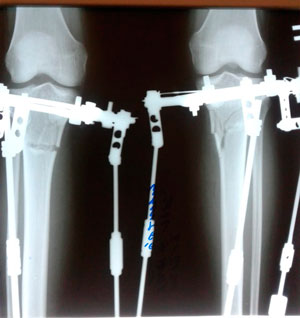

Исходник - 34 года. Южная Корея.

Дата операции - 18.11.2019.